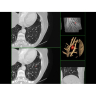

Кардиология

• Неинвазивная оценка состояния коронарных артерий.

• Диагностика атеросклероза и других сердечно-сосудистых патологий.